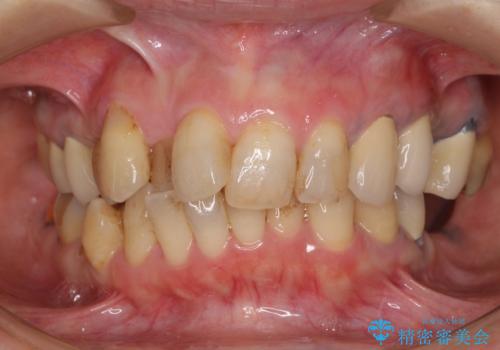

ノンクラスプデンチャー(金属止め具のない入れ歯)で左側の咬合回復

- 奥歯が痛いことを主訴にご来院された患者様です。入院してしまい、治療を2年間放置してしまったとのことでした。

左上は、抜歯とブリッジ治療を行いました(抜歯前に医師と対診)。

左下は、現在も抗がん治療を続けているため、観血的処置(インプラントなどの外科)はなるべく避けたいとのことで入れ歯を希望されました。それに伴い、入れ歯を支える歯のクラウンやりかえも行いました。

患者様はインプラント等の外科処置は希望されなかったため、セラミックと義歯で治療を行いました。

義歯を製作する際は、支えとなる歯の治療も同時に行うことで、義歯の製作が容易になります。

今回もそのように製作したところ、適合がよく安定のよい義歯になりました。患者様本人も使っていて全く痛くないとのことで、追加の調整もなく使用して頂いてます。患者様には、大変満足して頂きました。